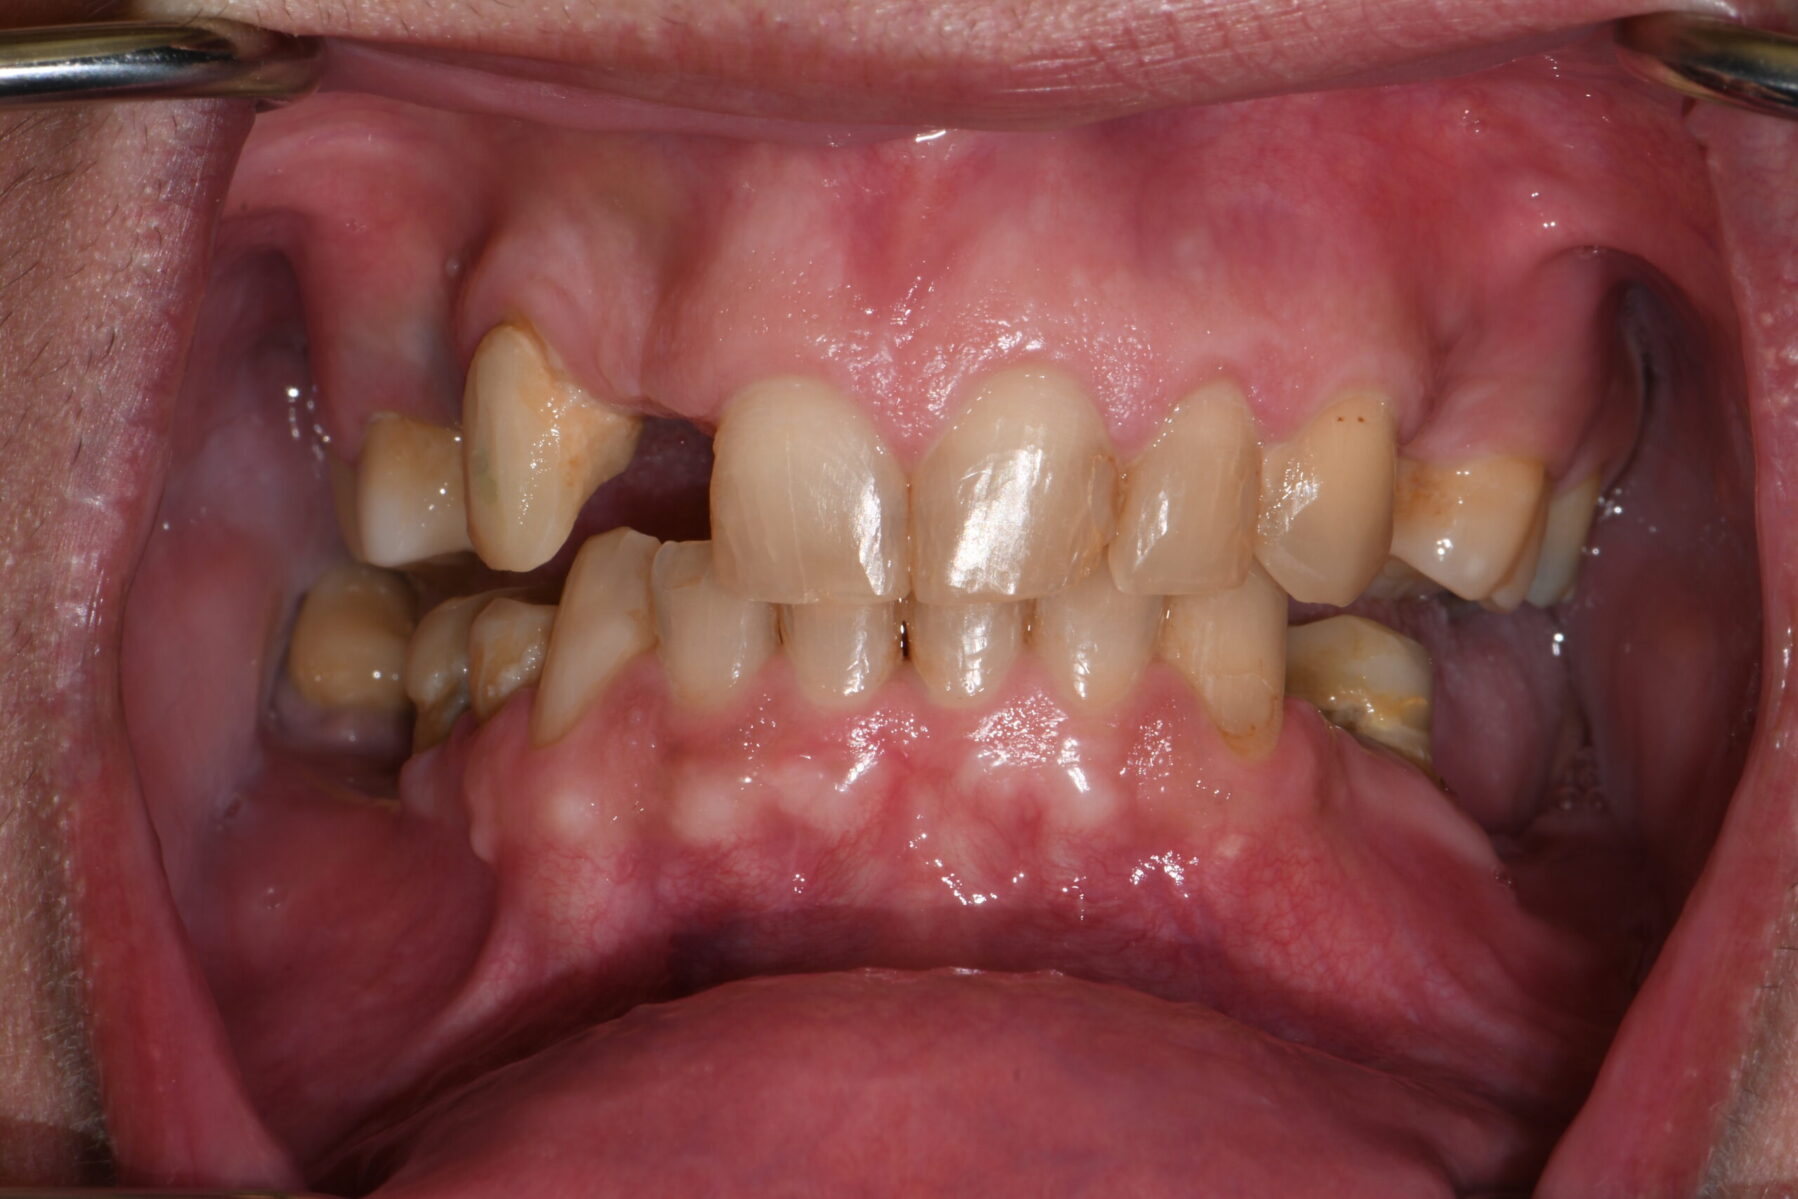

Full mouth rehabilitation encompasses a range of restorative dental procedures aimed at restoring the function, health, and esthetics of your entire mouth.

This may involve the use of crowns to protect and reinforce weakened teeth, dental implants to replace missing teeth, and veneers to improve the appearance of discolored or damaged teeth. Each treatment is tailored to match the color, shape, and size of your natural teeth, ensuring a cohesive and beautiful smile.

• Restoring multiple missing or damaged teeth for improved function and stability

• Restoring worn down teeth from grinding, clenching, or traumatic occlusion